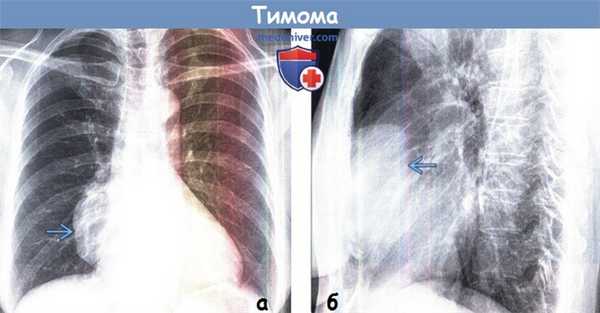

На рентгенограмме грудной клетки тимома имеет вид объемного образования неправильной формы, расположенного в переднем средостении. КТ грудной клетки значительно расширяет объем информации, полученный при первичной рентгендиагностике и в ряде случаев позволяет поставить морфологический диагноз. Уточнение локализации и взаимоотношения новообразования с соседними органами при КТ средостения позволяет в дальнейшем выполнить трансторакальную пункцию опухоли средостения, что чрезвычайно важно для гистологического подтверждения диагноза и верификации гистологического типа тимомы.

2. Рентгенография тимомы:

• При тимомах бессимптомных или небольшого размера патологические изменения при рентгенографии могут не визуализироваться

• Изолированное объемное образование переднего средостения:

о В любом месте на протяжении от верхней апертуры грудной клетки до кардиодиафрагмального угла

о Узловое утолщение передней соединительной линии

о Изменение контуров средостения при рентгенографии в прямой проекции

о Контур четкий ровный или дольчатый

о Обычно односторонняя локализация, реже-двухсторонняя

о Могут выявляться кальцификаты

о При рентгенографии в боковой проекции определяется узелок или объемное образование в переднем средостении

о Крупная тимома: объемное воздействие на прилежа щие структуры

о Инвазивная тимома:

- Инвазия легкого: контур неровный или спикулообразный

- Инвазия диафрагмального нерва: высокое стояние купола диафрагмы, паралич диафрагмы

- Метастазы в плевре: узелки в плевре; могут прогрессировать до циркулярного узлового утолщения плевры

(а) У пациента с тимомой при рентгенографии органов грудной клетки в ПП проекции в правой половине средостения определяется объемное образование с четким дольчатым контуром. При рентгенографии в прямой проекции тимомы обычно проявляются изменением контура средостения.

(б) У этого же пациента при рентгенографии органов грудной клетки в боковой проекции видно, что тимома располагается в переднем средостении. Рентгенография в боковой проекции позволяет установить локализацию объемного образования в одном из трех отделов средостения и сузить дифференциальный ряд заболеваний.